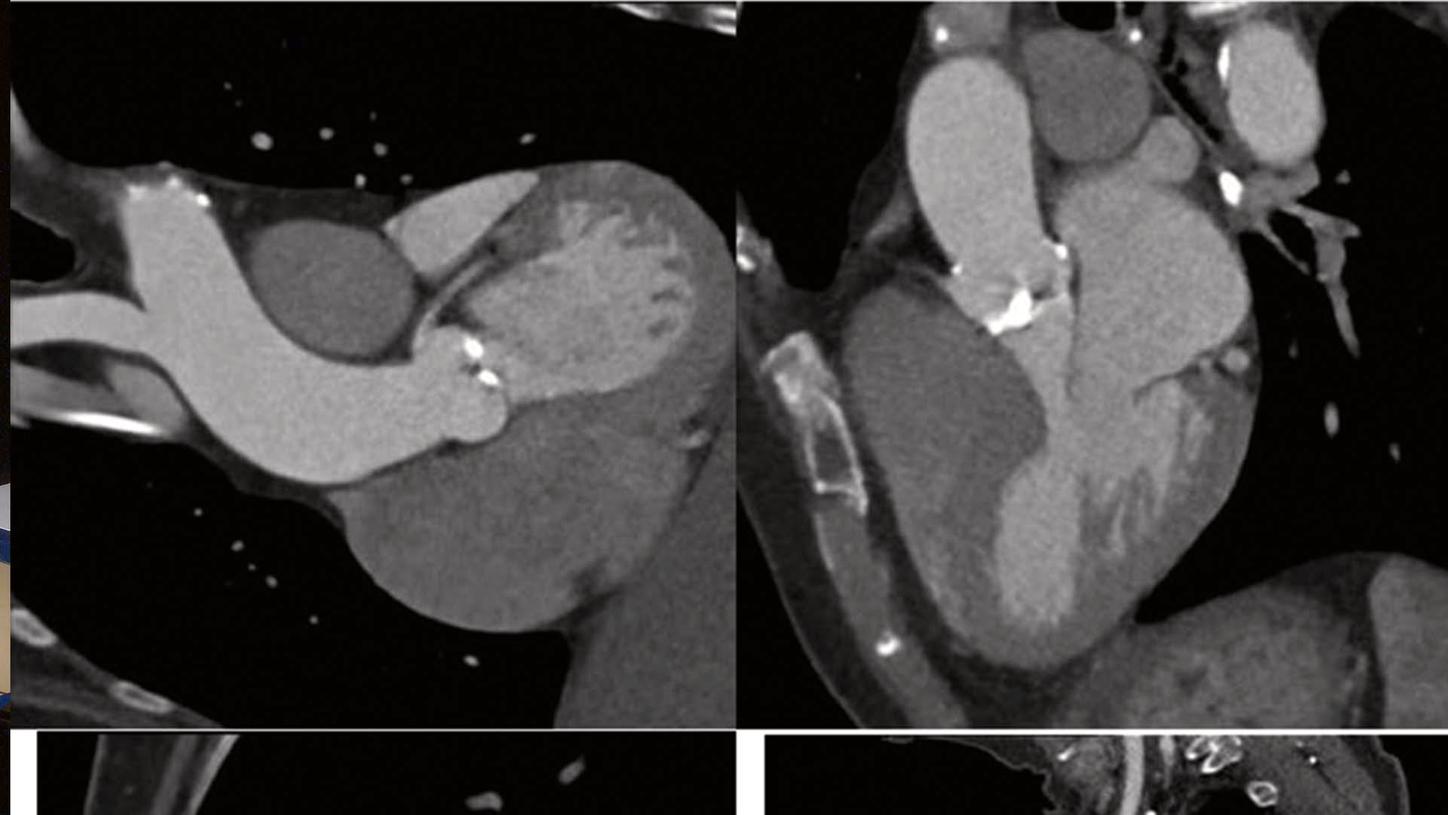

Application Training for Computed TomographyCourse overview - explore our offerings

These courses are offered as classroom training in our Training Centers or as as virtual classroom training independently where you are located. Theoretical principles of imaging are supplemented by a wide range of practical exercises, giving you the opportunity to gain skills for day-to-day clinical work. In our virtual courses we impact practical knowledge in clear, manageable units and focus on retaining the interactive approach that you are familiar with from our face-to-face training. Learn in the virtual work space and benefit from innovative digital methods.